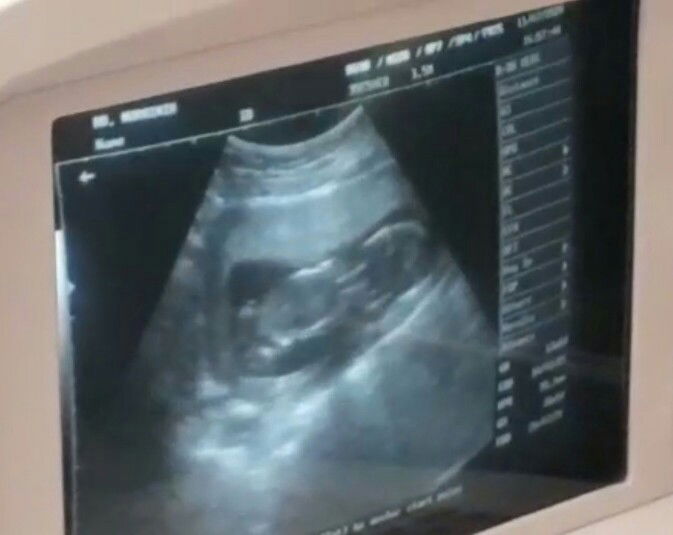

Minggu ke 6 lebih 4 hari

Apa yang bunda² rasakan? Share dong bun Belum pengalaman, baru hamil yang pertama ini. Kalau ngerasa sesuatu kadang parnoan sendiri soalnya??